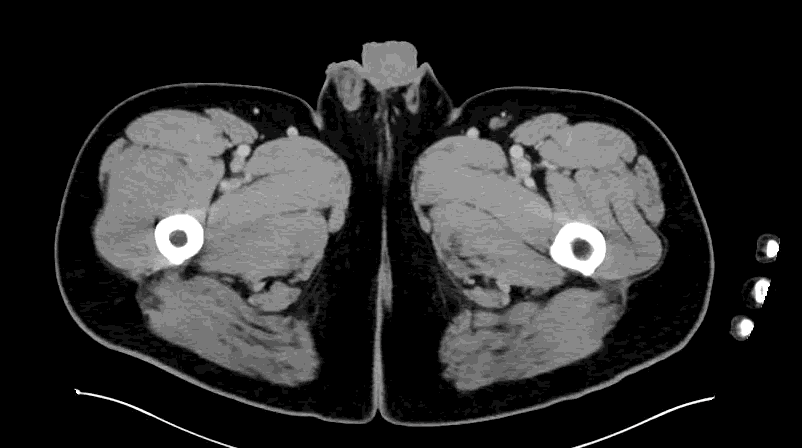

CT impression :

Right lower quadrant mid ileum 5.4 x 3.5 x 3.3 cm diverticulum, which may represent Meckel's diverticulum, containing calcifications/stones. Surrounding inflammatory fat infiltration suggesting Meckel's diverticulitis. Proximal small bowel distention with air-fluid levels, which may represent ileus versus partial small bowel obstruction. Unremarkable appearing appendix.

Surgery was consulted. Patient was admitted under surgery for planned for diagnostic laparotomy, possible exploratory laparotomy, possible diverticulectomy, possible small bowel resection.